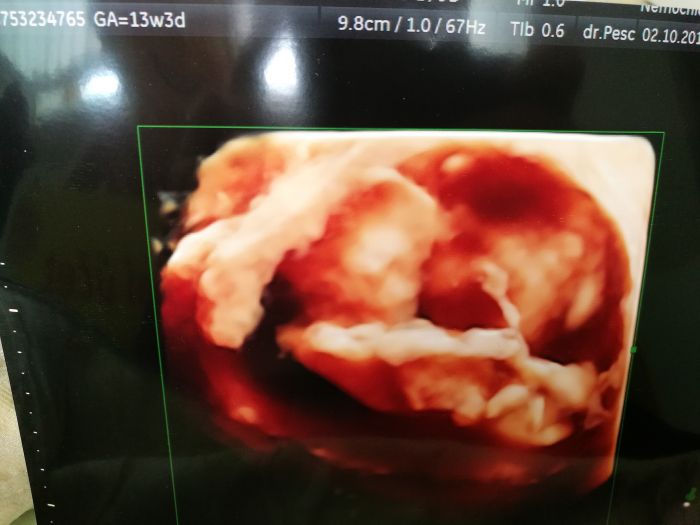

Devcata jdu se pochlubit dobrou zpravou, treba vam to trochu zvedne naladu a da nadeji, my se snazili rok a po jednom potratu jsem ve 14tt. Dnesni prvni screening dopadl skvele, jen mam vyssi riziko cukrovky 1:83, ale to mi je uplne fuk, mam si koupit nejaky doplnek stravy a byt v klidu. Vypada to na holcicku, ale nechtela se moc ukazovat, priste uz mi to rekne na 100%, mimco sebou strasne mrskalo, doktor se smal, ze ho snad ami nezmeri, poslouchali jsme srdicko, chlap byl uplne nadsenej. Velikost odpovida, takze termin zustava 6.4. Vysetreni bylo fajn, chlap se s panem doktorem zna z hokejbalu, jeho syn hraje s nasim v tymu a me pan doktor ucil na zdravce. Vubec nevim ceho jsem se tak bala. Vysledky mi jeste bude volat nejaka doktorka, ale podle zltrazvuku nam to vyslo bajecne.